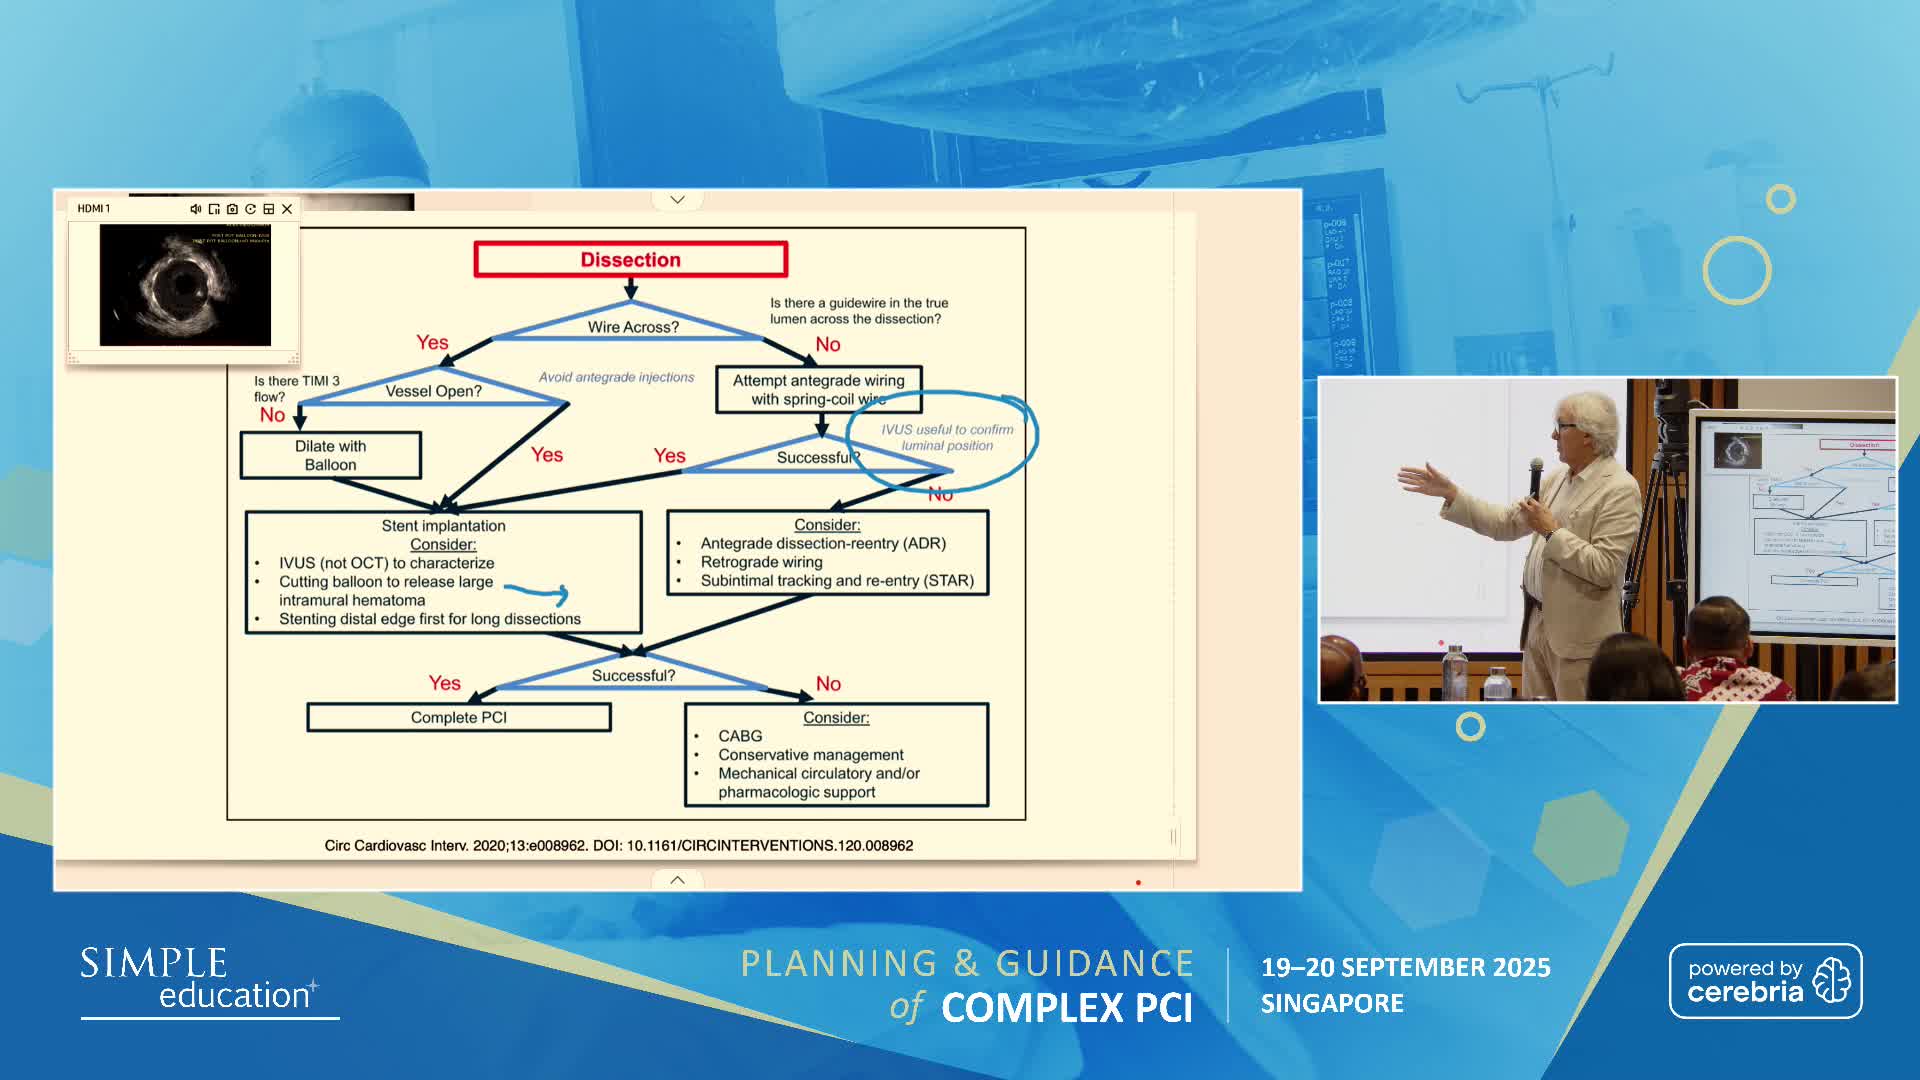

Planning and guidance of complex percutaneous coronary interventions - June 2023 Day One

Planning and guidance of complex percutaneous coronary interventions - June 2023 Day Two

Planning and guidance of complex percutaneous coronary interventions - October 2022 Day One

Planning and guidance of complex percutaneous coronary interventions - October 2022 Day 2

Planning and Guidance of Complex Percutaneous Coronary Interventions - May 2022 Day One

Planning and Guidance of Complex Percutaneous Coronary Interventions - May 2022 Day Two

Planning and Guidance of Complex PCI 23rd November 2021

Planning and Guidance of Complex PCI 22nd November 2021

Planning and Guidance of Complex PCI 12th April 2021

Planning and Guidance of Complex PCI 13th April 2021